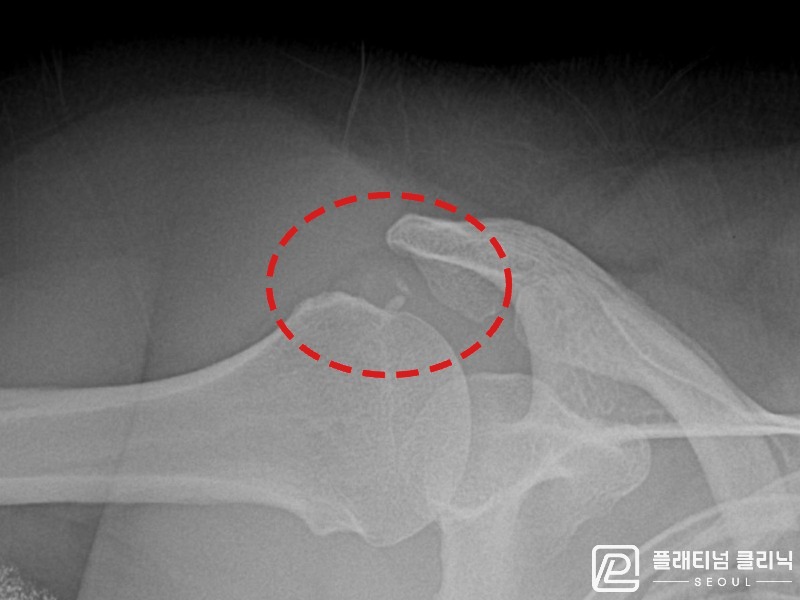

[촬영시기:21.11.04~21.11.09]

[석회분쇄흡입술] 우측 어깨 극심한 야간 통증으로 수면이 불가능해진 50대 여성 환자로, X-ray에서 우측 극상근건 내 석회 침착이 확인되어 석회분쇄흡입술을 시행하였습니다.